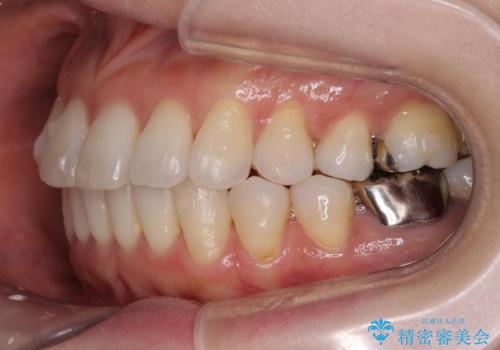

- 突き出た前歯の角度を改善したい、と矯正治療を希望され来院されました。

抜歯を行いワイヤー矯正で2-3年程度の時間をかけて、しっかり前歯を後方に移動させるか、

抜歯を行わずにIPR(歯の間に空隙を設ける)で可及的に角度の改善を行うか、

2通りの治療方針をご提案しました。

治療期間が約半年で行うことができ、歯を抜かずにマウスピース矯正で可及的に前歯の角度を改善する治療方針を

奥歯の状態等も鑑みて選択されました。

約半年で大きく前歯の角度を改善することができ、抜歯を行わない矯正治療の結果に大変喜んでいただくことができました。